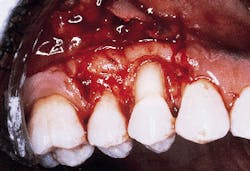

Photograph #3 is a view of a defect after thorough debridement. The periodontal disease process has resulted in an osseous dehiscence which extends 6 mm from the cementoenamel junction to the osseous crest on the mid-facial aspect of the involved premolar.

Photograph #3: This photograph demonstrates the root surface subsequent to degranulation and root debridement. Hand instruments and ultrasonic scalers were employed to detoxify the root surface.